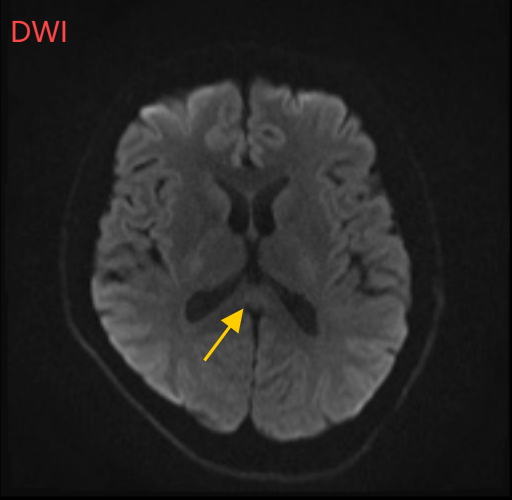

医生摇摇头,经过头部磁共振平扫、弥散、增强影像等检查,医生诊断,小董是得了一种比较少见的病症:可逆性胼胝体压部综合征。

小董的影像结果显示,胼胝体压部发生病变

经过一周治疗,小董的胼胝体压部病变明显好转